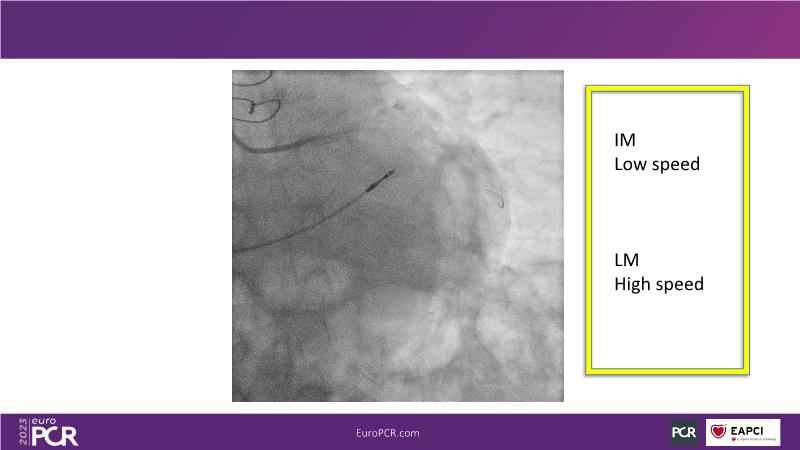

The aim of this session is to address the question of how to optimise outcomes for high-risk patients by analyzing two real-life cases for discussion: a distal calcified left main trifurcation and a high-risk PCI with orbital atherectomy.